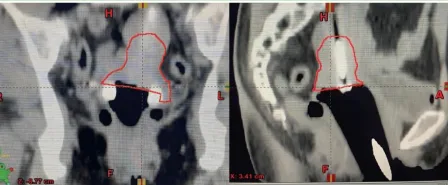

在全球范圍內(nèi),每年大約有20萬名女性死于宮頸癌。在我國,宮頸癌是女性中最普遍的惡性腫瘤之一。目前,宮頸癌的三大主要治療方式包括手術(shù)、放療和化療,其中放療應(yīng)用最廣泛,適合各期宮頸癌患者。三維近距離后裝放射治療技術(shù)能夠在提高腫瘤部位的放射劑量的同時,減少對正常組織的放射損傷,從而降低放射治療的副作用。 近距離后裝放療是“內(nèi)照射”的一種方法,與遠(yuǎn)距離放射治療(外照射)相對。該治療方式將放射源直接置入需治療的區(qū)域,對于宮頸癌患者而言,放射源將被放置于宮頸腫瘤部位進(jìn)行局部照射。若將腫瘤比作敵軍,外照射則如同廣泛布陣,全面覆蓋,但為盡量減少對周圍健康組織的損害,其放射劑量相對較低。而內(nèi)照射則如同對敵軍指揮中心的精準(zhǔn)打擊,劑量較高,集中性強(qiáng)。因此,若缺少內(nèi)照射這一環(huán)節(jié),便缺少了對敵軍指揮中心的精準(zhǔn)打擊,從而增加了腫瘤復(fù)發(fā)的風(fēng)險。 什么是三維近距離后裝放療? 三維近距離后裝放療,是先將施源器放置于接近腫瘤的人體天然腔、管道內(nèi)(如宮腔、陰道等)或?qū)⒖招踞樄苤踩肓鲶w內(nèi);隨后,利用CT或磁共振成像技術(shù)掃描獲取圖像數(shù)據(jù),通過圖像傳輸系統(tǒng)將這些數(shù)據(jù)導(dǎo)入治療計劃系統(tǒng),醫(yī)生根據(jù)患者病情需要確定靶區(qū)范圍,經(jīng)計劃系統(tǒng)計算劑量分布,在獲得理想治療方案后,對腫瘤實(shí)施放射治療。 三維近距離后裝放療的優(yōu)勢 1三維近距離后裝放療每次治療時都有實(shí)時CT/核磁共振圖像引導(dǎo),彌補(bǔ)了二維腔內(nèi)放療不能直視腫瘤的缺陷,能更精確覆蓋腫瘤或瘤床范圍,達(dá)到更好的靶區(qū)覆蓋,實(shí)現(xiàn)靶區(qū)劑量的個體化分布,提高患者生存率,顯著降低復(fù)發(fā)率。 2 三維近距離后裝放療是在CT/核磁共振圖像引導(dǎo)下進(jìn)行的,在圖像上精準(zhǔn)勾畫靶區(qū)和危及器官,后裝計劃系統(tǒng)可以對放射源駐留位置、處方劑量等預(yù)設(shè)參數(shù)進(jìn)行優(yōu)化,提高腫瘤靶區(qū)的照射劑量、降低周圍正常組織的照射劑量。同時應(yīng)用多模態(tài)影像管理系統(tǒng),客觀地在三維的參考面對腫瘤及周邊危及的器官進(jìn)行評估,在保證腫瘤區(qū)域受照劑量的同時,有效保護(hù)膀胱、直腸、小腸等危及器官,減少急性放射性黏膜損傷的發(fā)生。 兩例宮頸癌患者 后裝治療前后影像學(xué)資料 病例1 病例2 門診預(yù)約方式 關(guān)注“滄州市中心醫(yī)院”微信公眾號,或支付寶關(guān)注“滄州市中心醫(yī)院互聯(lián)網(wǎng)醫(yī)院”,點(diǎn)擊“醫(yī)療服務(wù)”—“掛號服務(wù)”—“放化療科—婦科、血液與皮膚軟組織腫瘤放療科”—掛號即可。 科室簡介 滄州市中心醫(yī)院婦科、血液與皮膚軟組織腫瘤放療科(放療三科)擅長各種腫瘤的放化療、靶向、免疫、腔內(nèi)后裝等中西醫(yī)結(jié)合的綜合治療;尤其擅長宮頸癌、子宮內(nèi)膜癌、陰道癌、外陰癌、卵巢癌、輸卵管癌等婦科腫瘤,以及淋巴瘤、骨髓瘤、黑色素瘤、骨腫瘤、軟組織腫瘤、皮膚腫瘤、罕見腫瘤、良性病變等疾病的綜合治療。 科室電話:0317-2072318 團(tuán)隊成員介紹 高雅麗 婦科、血液與皮膚軟組織腫瘤放療科(放療三科)主任,醫(yī)學(xué)博士,副主任醫(yī)師,碩士生導(dǎo)師;河北省“三三三”第三層次人才;曾于北京協(xié)和醫(yī)院、山東省腫瘤醫(yī)院進(jìn)修學(xué)習(xí);發(fā)表SCI論文4篇,中文核心期刊10余篇,獲得河北醫(yī)學(xué)會科技進(jìn)步一等獎1項;河北省抗癌協(xié)會近距離放射治療專業(yè)委員會常務(wù)委員;河北省女醫(yī)師協(xié)會精準(zhǔn)醫(yī)療專業(yè)委員會常務(wù)委員等。 擅長:各種腫瘤的放化療,尤其擅長婦科腫瘤、淋巴瘤及骨與皮膚軟組織等腫瘤的綜合治療。 電話:15932736182 宋麗娜 主治醫(yī)師,腫瘤學(xué)碩士,畢業(yè)于河北醫(yī)科大學(xué);河北省抗癌協(xié)會放療專業(yè)委員會委員 河北省腫瘤防治聯(lián)合會近距離放射治療專業(yè)委員會委員;2021年于北京協(xié)和醫(yī)院進(jìn)修學(xué)習(xí)。 擅長各種惡性腫瘤的診斷、放療及綜合治療,尤其擅長婦科腫瘤、骨與皮膚軟組織腫瘤及淋巴瘤等腫瘤的放療和綜合治療。 電話:13643376566 王志聰 主治醫(yī)師,腫瘤學(xué)碩士,畢業(yè)于河北醫(yī)科大學(xué);參與國家自然科學(xué)基金項目1項,發(fā)表SCI 1篇。 擅長各種惡性腫瘤的放化療、分子靶向及生物免疫治療,對宮頸癌,子宮內(nèi)膜癌,卵巢癌,肺癌,乳腺癌,胃癌、結(jié)直腸癌、骨與皮膚軟組織腫瘤的治療有一定的治療經(jīng)驗。 電話:13111712797 居欣月 醫(yī)師,腫瘤學(xué)碩士,畢業(yè)于吉林大學(xué);發(fā)表SCI及核心期刊各一篇,對婦科腫瘤、肺癌、結(jié)直腸癌、淋巴瘤、骨髓瘤等腫瘤有一定的治療經(jīng)驗。 擅長肺癌、結(jié)直腸癌、淋巴瘤、骨髓瘤的放化療及靶向治療。 電話:15383941314 劉冰倩 醫(yī)師,腫瘤學(xué)碩士,畢業(yè)于河北醫(yī)科大學(xué),對各種實(shí)體惡性腫瘤尤其是婦科腫瘤的放化療,靶向及免疫治療等有一定的經(jīng)驗。 電話:19031776170 鄭路雨 醫(yī)師,腫瘤學(xué)碩士,畢業(yè)于首都醫(yī)科大學(xué);參研多項省市級科研課題,以獨(dú)立第一作者身份發(fā)表SCI一篇,專注于宮頸癌、子宮內(nèi)膜癌、卵巢癌等婦科腫瘤以及各種淋巴瘤的治療。 電話:18333790410 彭夢瑩 醫(yī)師,腫瘤學(xué)碩士,畢業(yè)于錦州醫(yī)科大學(xué);以第一作者身份發(fā)表SCI論文一篇,對宮頸癌、子宮內(nèi)膜癌、卵巢癌等婦科腫瘤以及皮膚腫瘤的治療有一定的研究。 電話:18712908752